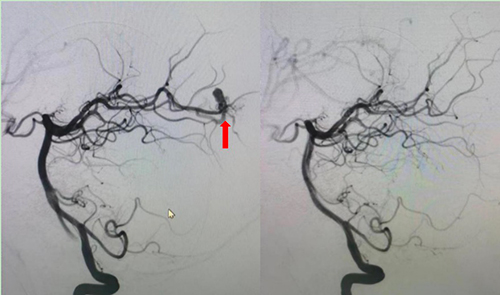

考虑到此次小明博病情复杂,葛明主任与彭芸主任、吴荣昌医生充分沟通患儿病情后,决定先于8月10日行全脑血管DSA造影术,充分了解畸形血管情况后再决定是否介入进一步栓塞治疗。造影显示,患儿为右侧大脑后动脉远端动静脉畸形,可以采用栓塞方式封堵畸形血管团。为了给患儿尽快手术,葛明主任向北京儿童医院院长倪鑫进行了汇报,并得到院领导的全力支持。

图2 右侧椎动脉造影图右图箭头处:畸形的血管团,左图箭头处:畸形血管团消失,拆雷成功

经过完善的术前沟通与准备,8月13日上午10时,这台“右侧大脑后动脉动静脉畸形栓塞术”正式开始,手术由吴荣昌医生主刀,郑铁华主任医师负责麻醉,杨雪护士长跟台。为进一步确保手术安全,吴荣昌医生邀请了天坛医院神经介入中心的刘恋主任指导手术。11时15分,手术顺利结束,术中造影显示小明博右侧大脑后动脉的畸形血管团被充分栓塞,藏在小明博颅内的这颗“雷”被顺利的拆除了。术后小明博没有发生偏盲、失明等并发症。术后6小时复查CT,小明博颅内血肿已经较前吸收,看到手术成功,家长悬着的心也终于放下了。